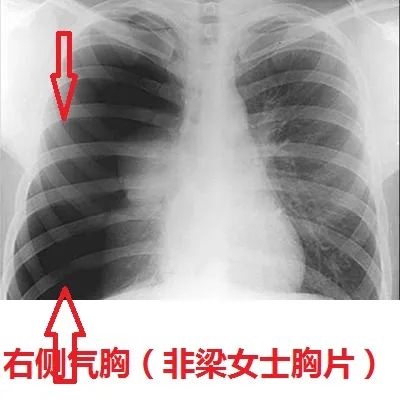

床旁胸片提示右侧大量气胸,红色箭头指示气胸线

右侧气胸